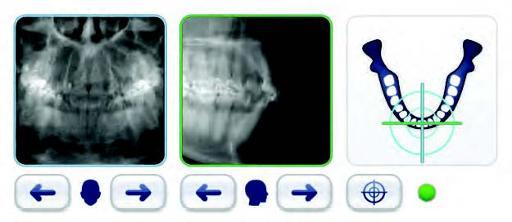

Dentists and clinicians can adeptly move from 2D to 3D like never before! With the touchscreen panel, choosing from a variety of region-specific 2D scan options or selecting the location and size of 3D FOV is simple and convenient. The GXDP-700™ offers 33 panoramic options — 11 projections for three patient sizes, two 3D volume sizes plus a dose-saving scout view, and the ability to add cephalometrics — 15 options, 5 projections for three patient sizes.

Your 3D workflow couldn’t be easier. After positioning the patient, use PerfectScout™ to zone in on the area of interest. This unique feature captures two, low-dose perpendicular images which display on the touchscreen panel. From there, the area of interest can be targeted — simply drag the crosshair into position, and then, initiate the scan.